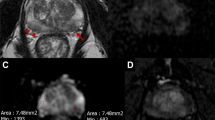

Prostate cancer (PCa) is the second most prevalent cancer among men worldwide [1]. Nevertheless, the mortality rate is relatively low, and most patients die with and not of PCa [2]. Timely and accurate diagnosis is therefore of utmost importance to avoid overtreatment of men with indolent, clinically insignificant PCa, and to offer radical curative treatment to men with life-threatening, clinically significant PCa (csPCa) [3]. Present-day guidelines advise the use of multiparametric magnetic resonance imaging (mpMRI) prior to biopsies [3], as it can noninvasively discriminate patients with indolent PCa from those with csPCa, retaining a high sensitivity for csPCa [4,5,6]. Using the version 2 of the Prostate Imaging Reporting and Data System (PI-RADS) [7], radiologists make a semiquantitative assessment of each suspicious lesion observed on mpMRI and assign a corresponding csPCa likelihood score, from 1 to 5. Together with clinical variables, such as patient age, prostate-specific antigen (PSA) levels, and family history, PI-RADS scores help clinicians determine whether further investigation (via systematic or targeted biopsies) is needed to make a final diagnosis.

Table 1 provides an overview of 17 public datasets for prostate MRI, which were found by the authors through their collaborative role in this research field and was updated with additional internet searches (i.e., The Cancer Imaging Archive, Zenodo, XNAT, GitHub, and grand-challenge.org). A total of 3,369 prostate MRI cases (including some overlapping cases) are available, of which 2,238 cases primarily include mpMRI images acquired between 2003–2021 in Europe and the United States. All cases were provided as full 3D volumes, except for the QUBIQ21 dataset [17], which provided a single slice per case. A total of 412 cases were collected for anatomical segmentation tasks, whereas the remainder were collected for PCa detection and/or classification. The majority of cases were scanned with a 3-T scanner, whereas only 296 cases were scanned with a 1.5-T scanner. Scanner vendors include the following: Siemens (Siemens Healthineers, Erlangen, Germany), Philips (Philips Healthcare, Best, The Netherlands), and GE (General Electric Healthcare Systems, Milwaukee, WI, USA) for 2571, 446, and 110 cases, respectively. A total of 346 cases were scanned with endorectal coils, whereas the remaining were scanned with phased-array surface coils. In 2,240 cases lesion delineations are available and 56 cases have matching histopathologic section images obtained from radical prostatectomy specimen. Table 1 shows that clinical variables are available for some cases, e.g., 2,620 cases with an associated PSA level. The scans are available in Digital Imaging and COmmunications in Medicine (DICOM), ITK MetaImage or NIFTI format for 1,547, 1,580, and 242 cases, respectively. Total size of all open datasets (images, annotations, and meta-data) amounts to approximately 253 GB. In 2021, delineations of PCa lesions and prostatic zones for (parts of) the PROSTATEx dataset [18] were curated by an independent third-party and publicly released at [19].

As of May 6, 2022, the PI-CAI challenge [37] has publicly released 1,500 (of 12,500) cases [38] with a much stronger reference standard than that of the PROSTATEx challenge [29]. Additionally, PI-CAI reserves a hidden testing cohort of 1,000 cases, with histopathology-confirmed positives (Gleason grade > 1) and histopathology (Gleason grade < 2) or follow-up confirmed negatives, that will span the complete distribution of patients encountered in clinical routine. Data will be multivendor (3-T scanners from Phillips and Siemens) and multicenter (Radboudumc, Ziekenhuis Groep Twente, University Medical Center Groningen, Norwegian University of Science and Technology). Patient age, PSA density, PSA level and prostate volume will be provided for all cases. Expert-derived lesion delineations are provided for approximately 80% of all cases, and AI-derived lesion delineations (pseudo-labels) are provided for all cases, using a state-of-the-art csPCa detection developed at Radboudumc [48].